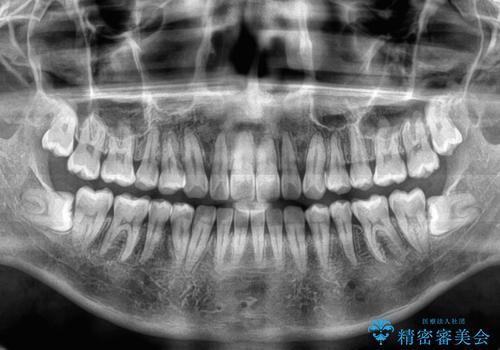

舌のトレーニングをしっかりと行ってくださったおかげで、順調に治療を終えることができました。

舌の突出癖が速やかに改善され、後戻りによるスペースは今のところ認められておりません。